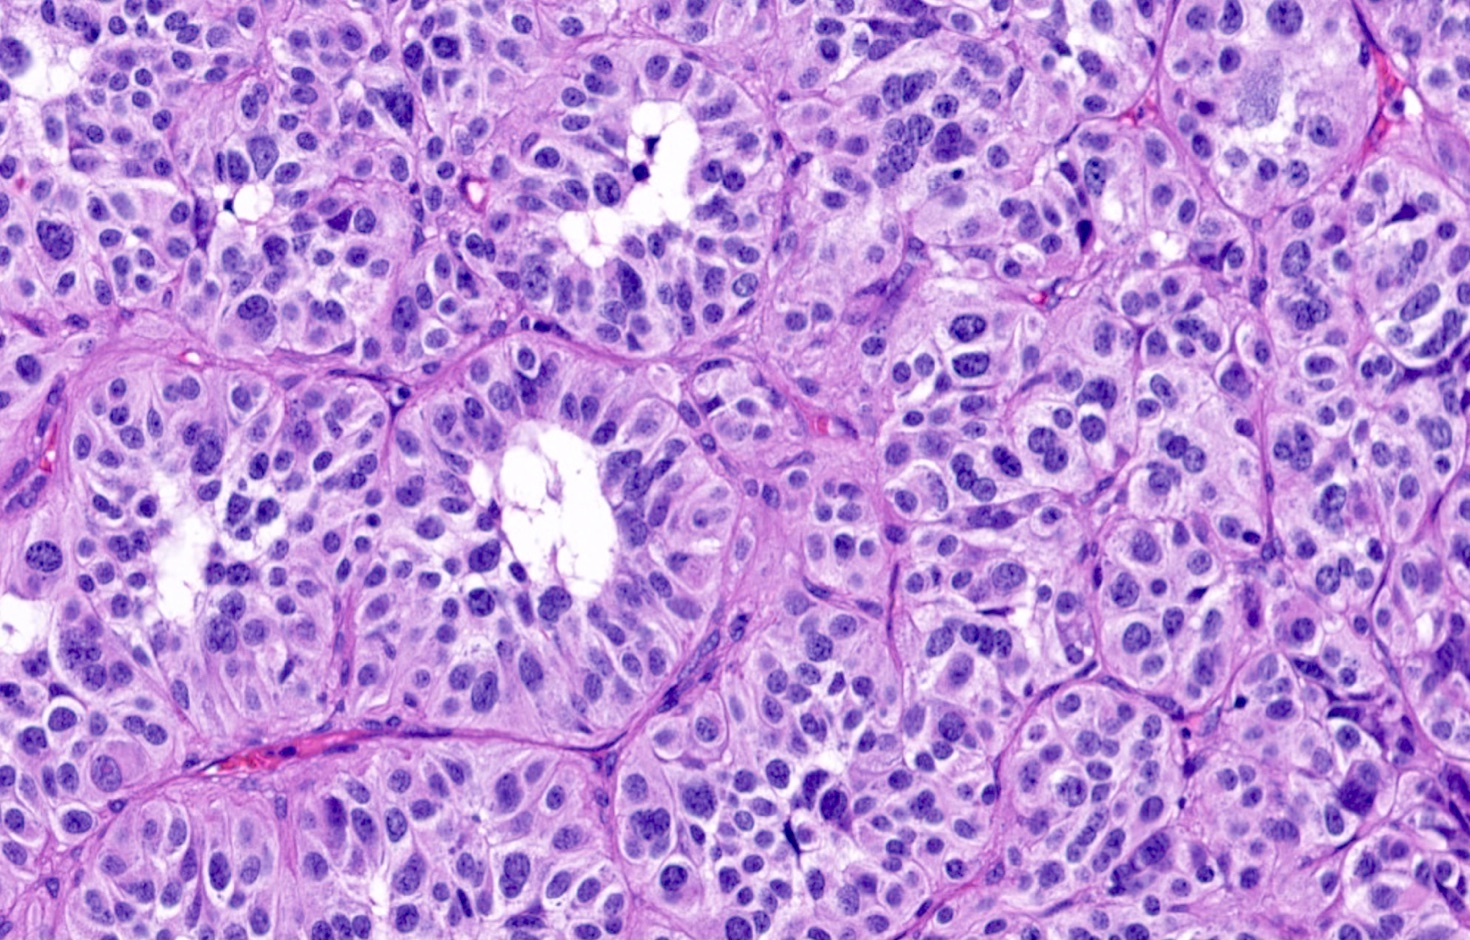

Microscopic (histologic) description

- Diagnostic criteria

- Neuroendocrine tumor with size ≥ 5 mm with < 2 mitoses/2 mm2 and absence of necrosis

- Neuroendocrine growth pattern (organoid, trabecular, rosette formation, nested) or pseudoglandular, follicular and papillary growth

- Tumor cells are uniform with a polygonal shape, round to oval nuclei with salt and pepper chromatin as well as inconspicuous nucleoli and moderate to abundant eosinophilic cytoplasm

- Spindle cells and clear cell features can be seen

- Stroma is fine and highly vascularized; hyalinization, cartilage or bone formation are possible

- Reference: Curr Oncol 2018;25:S86

Microscopic (histologic) images

Contributed by Philippe Joubert, M.D., Ph.D., Jijgee Munkhdelger, M.D., Ph.D. and Andrey Bychkov, M.D., Ph.D.

A 55 year old woman had a lower left lobectomy showing a well circumscribed flesh colored tumor. Histologic details are shown in the image above. Regarding this entity, which of the following statements is true?

Practice answer #1

A. CDX2 is usually negative in the lung and is useful to differentiate from a metastasis of an intestinal origin. The image shows a tumor with a trabecular pattern and pseudorosettes. The stroma is highly vascularized. Tumor cells are monotonous with scant to moderate eosinophilic cytoplasm. Nuclei are round to oval with salt and pepper chromatin and inconspicuous nucleoli. No mitoses are seen. These features are consistent with a typical carcinoid lung tumor.

Ki67 immunostaining, counter to well differentiated neuroendocrine tumors from the gastrointestinal tract, is not essential to grade the tumor. The difference between typical and atypical tumor relies on mitosis count and the presence of necrosis. However, Ki67 is useful to differentiate from high grade neuroendocrine tumors (small cell and large cell neuroendocrine carcinomas) on small biopsies with artifacts. TTF1 is positive in only half of cases with a higher frequency in peripheral tumors. Rb expression is preserved in typical carcinoid lung tumors, unlike in small cell tumors.